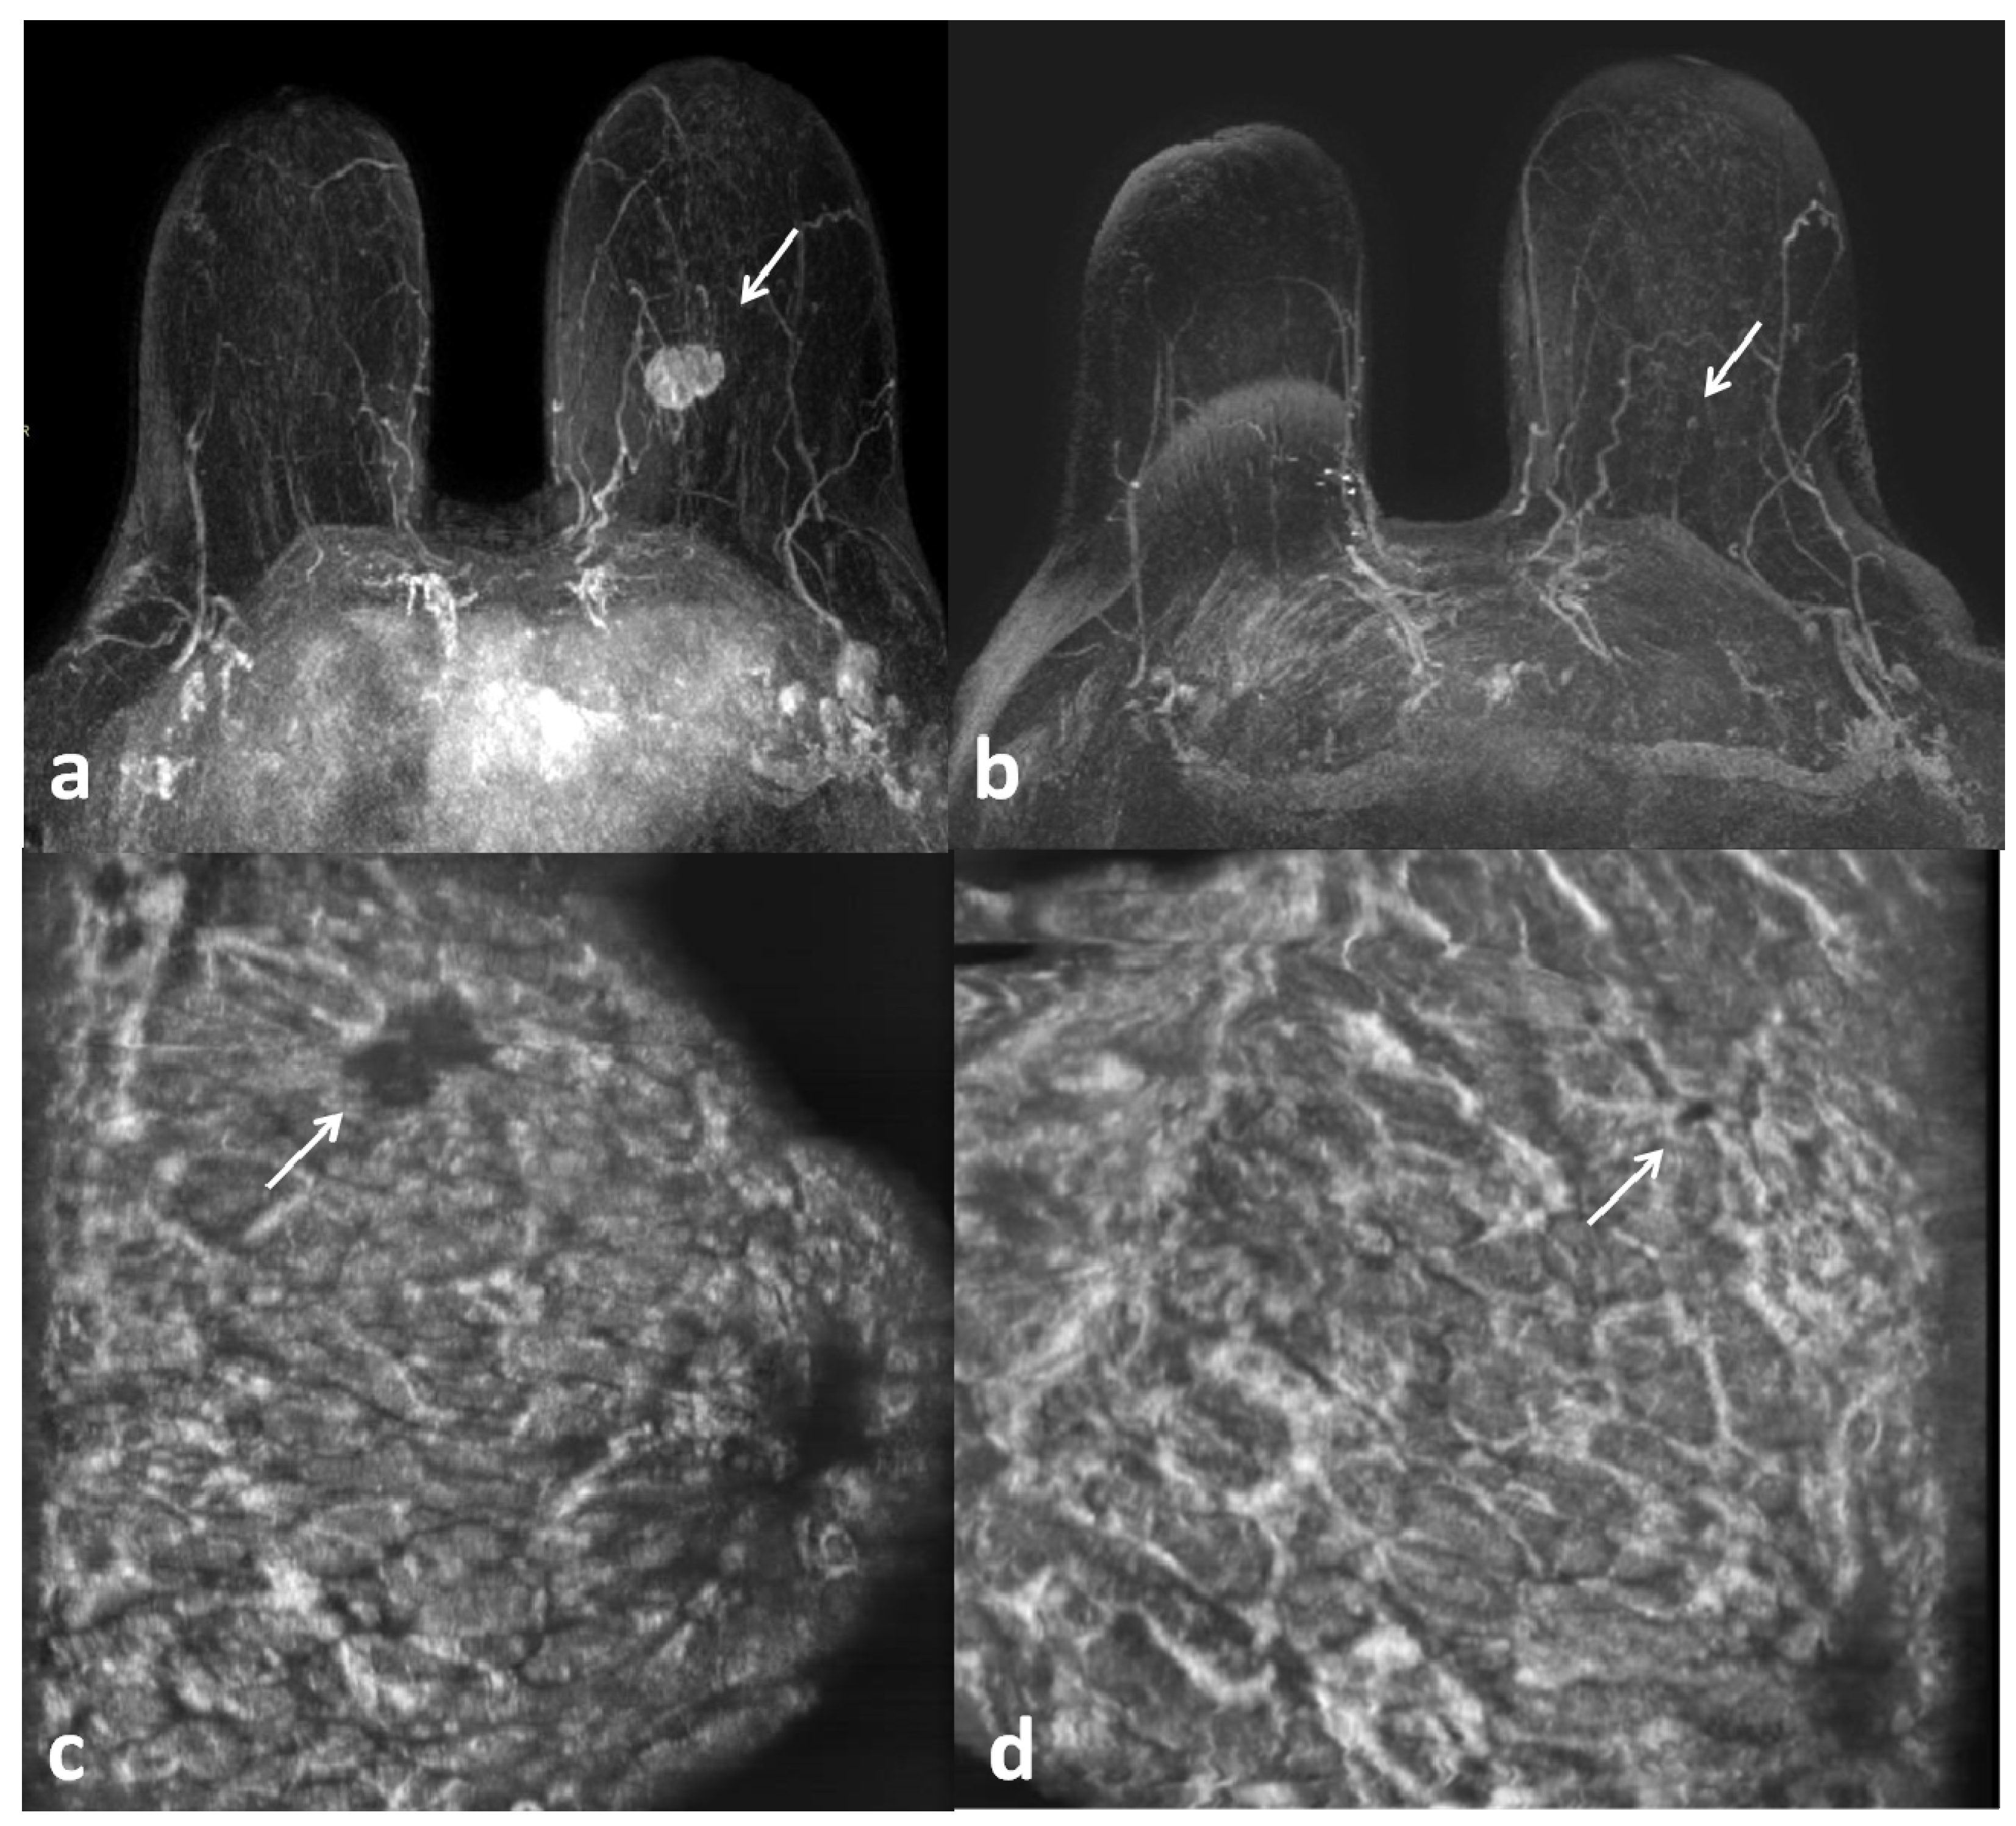

1. Introduction

2. Materials and Methods

2.3. ABUS Technique

2.4. Image Analysis

3. Results

4. Discussion